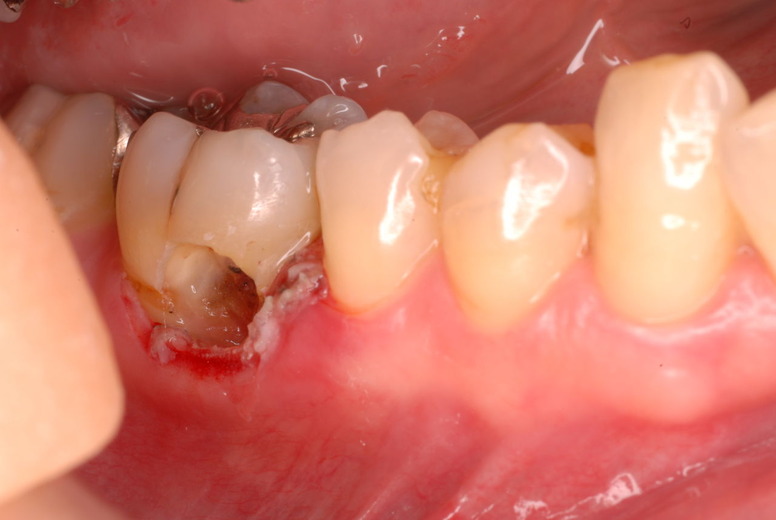

写真左下の親知らずが痛くなり抜歯しました。その後歯茎を除去して虫歯を露出させる処置を二回ほどしています。

レントゲンでは小さいですが、こう言う虫歯が一番怖いのです。

治療の成功率は極めて悪くすぐ再発しやすいのです。

隣の14歳大臼歯がひどい虫歯になり治療不可能になりつつある状態のレントゲン